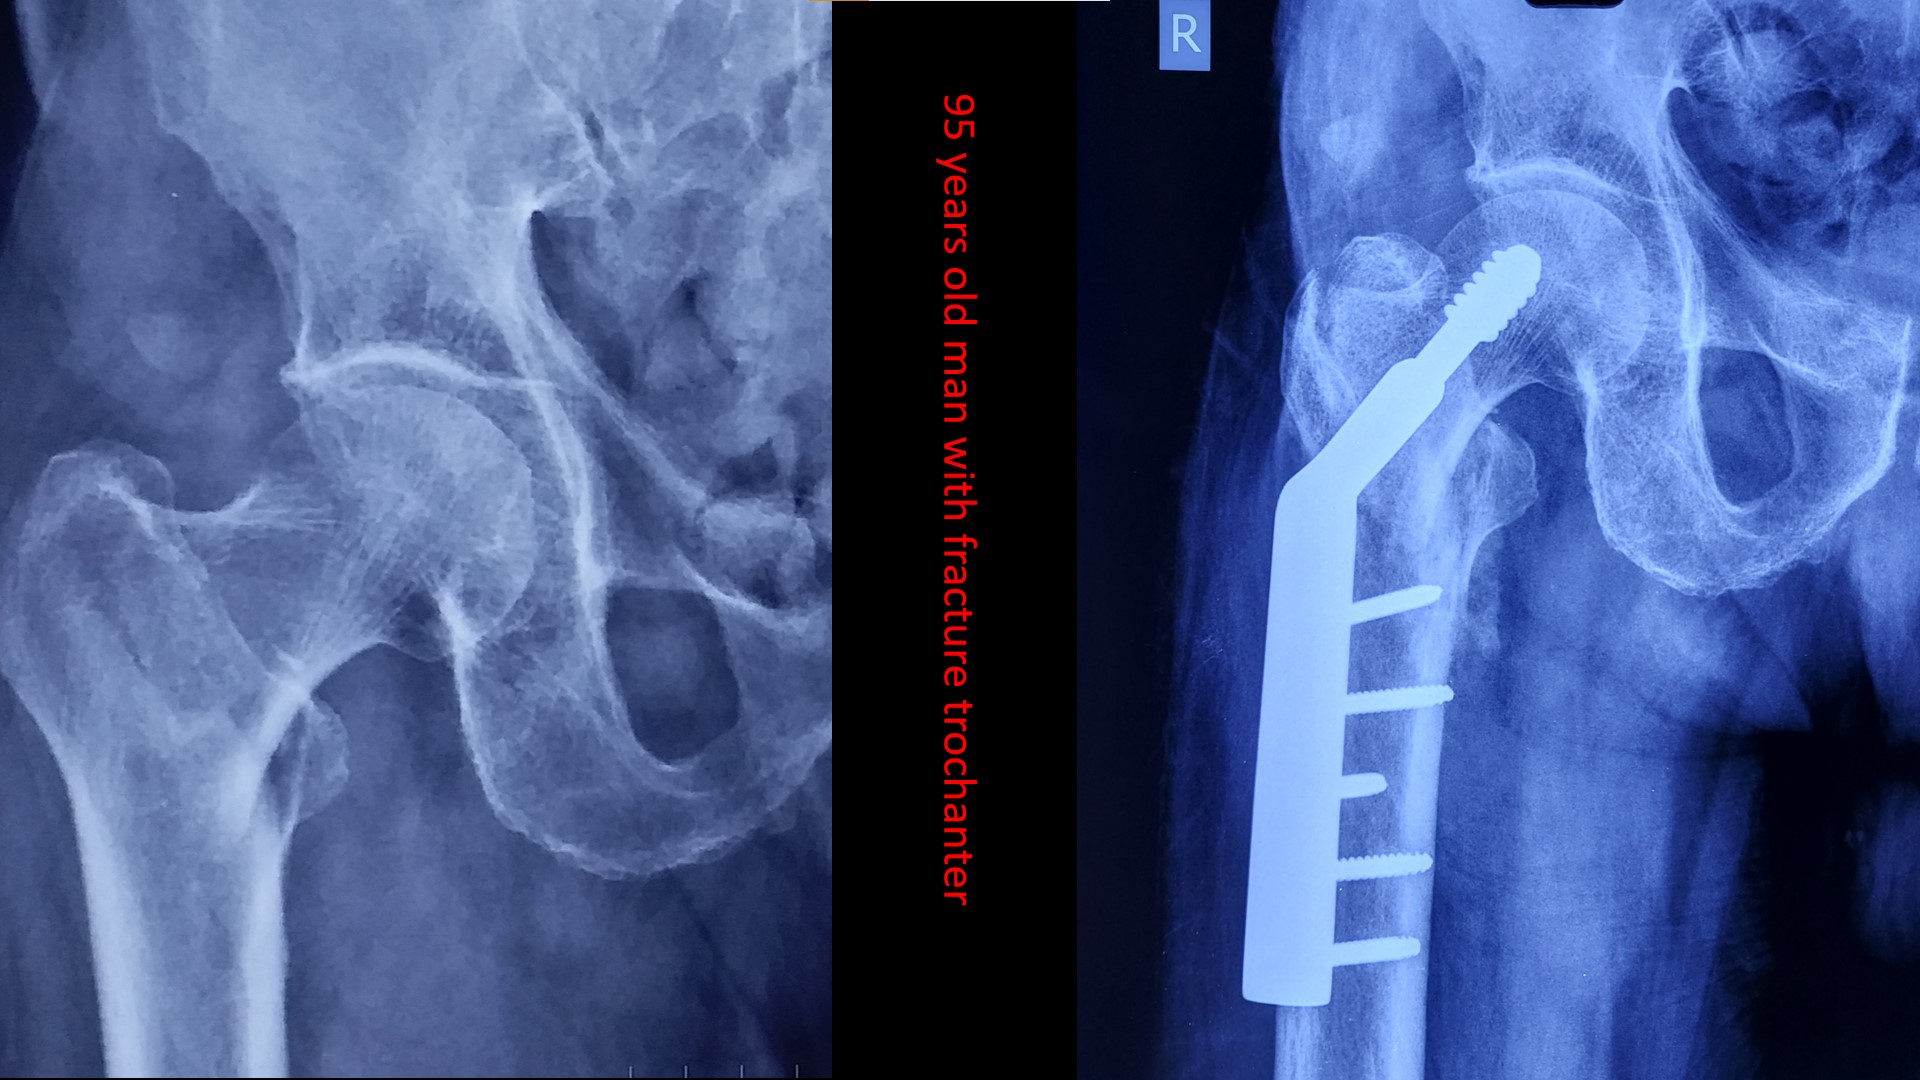

The care you deserve.

Please send us a message, or call us for an appointment. +919287283131,+9188166438,04662223131, 04662223785